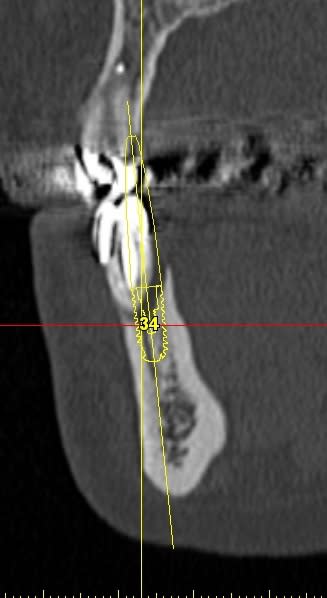

La rx avec bistouri en place sert à vérifier quoi?

la radio sert à vérifier la position de la lame 15, par rapport à la racine et au sinus, mais je ne suis pas sur que tu comprennes, que le bistouri est dans l'os, c'est l'instrument le plus fin et le moins traumatisant pour fendre l'os (je le préfère au piezzo et même au disque diamanté).